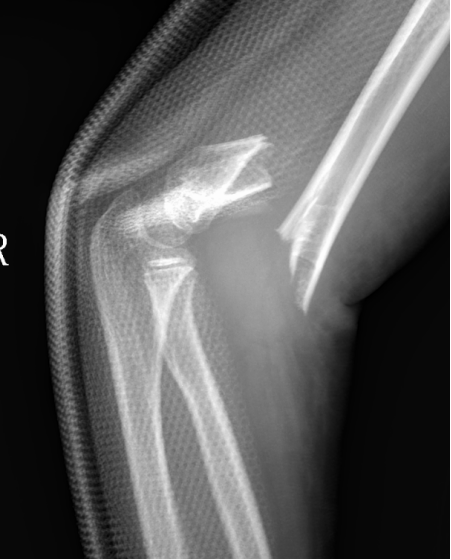

3、小林(化名):男、4岁、在家里从双层床上摔下致左肘部肿痛、畸形、活动受限4小时就诊我院。(下图为患儿术前X线片)

麻醉下手法整复经皮钢针内固定,术后患儿恢复良好。(下图为患儿术后X线片)